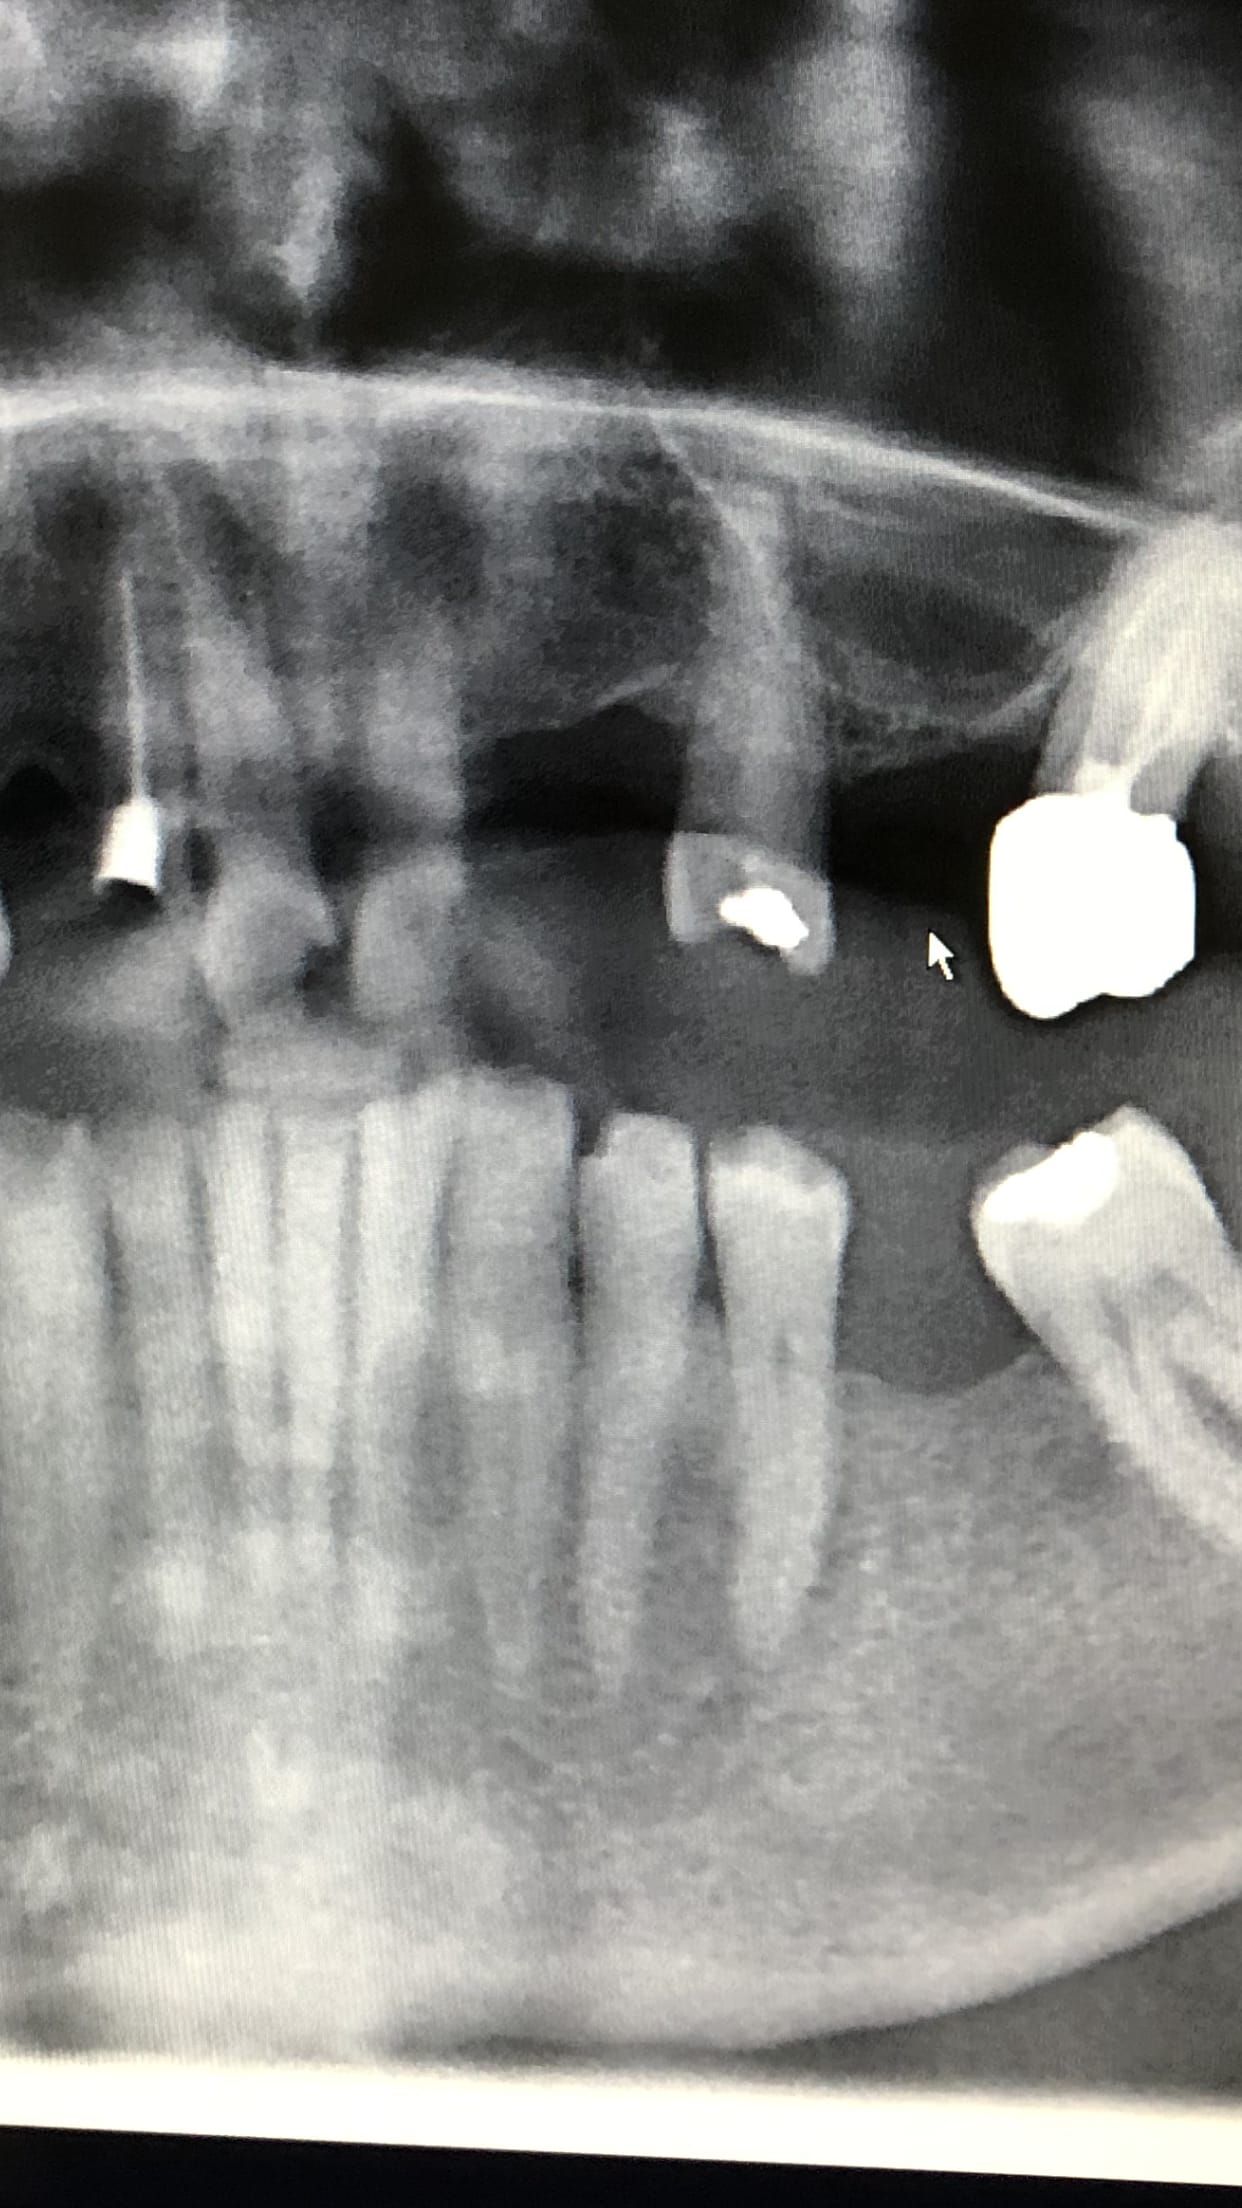

micromega

On voit pas grand chose ... radio la 12 avant

chicot,tu dis qu on voit pas grand chose...la 26 elle est comment?couronnee noçn? la 12 elle te parait pas a plat,la 24 complement usee la 11....ca te parait pas peter?

et en quoi ma pano de diagnostic est non indiquee?comprends pas ton argumentaire ..je n ai traitee que la 12,j ai les cliches recommandes,pour le reste la pano est pour moi suffisante .et la c est une photo de la pano,la qualite reelle est meilleure